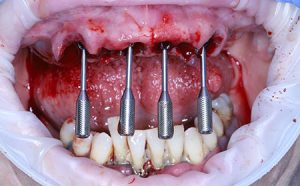

A patient in their fifties lost all their upper teeth due to poor dental hygiene over a long period of time. The patient came in after their tooth number 21 (8) broke and fell out. In the first phase, the upper arch was restored – extractions were performed on the upper arch, implants were placed, and the most suitable multi-units were chosen. For the anterior area, four angled multi-units were selected. As can be seen, the screw channels are parallel and oriented on the occlusal plane after correction. The support of the multi-unit helps predict the angle of the future screw channel. Each angled multi-unit is equipped with such a support.

Parallel positioning of the screw channel after angle correction.